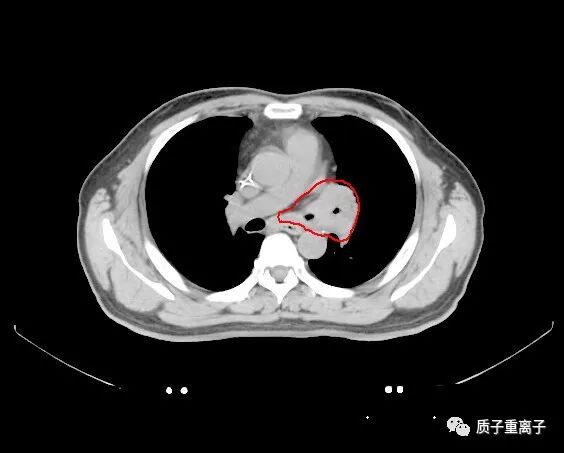

质子治疗前检查图像:左肺上叶占位性病变

病理检查:中分化角化型鳞癌